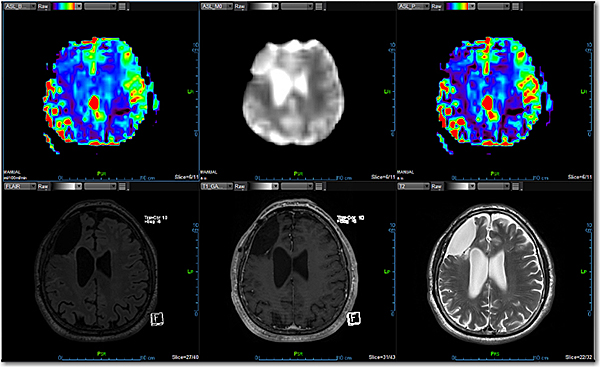

Додаток MR Neuro ASL

Додаток Neuro Arterial Spin Labeling (ASL) інтегровано в розширену візуалізацію Vitrea і забезпечує неінвазивне зображення для ефективного вимірювання перфузії.

Кількісне вимірювання мозкового кровотоку ASL без введення контрастної речовини та без випромінювання є ключовим компонентом педіатричної візуалізації

Має перевагу перед методами на основі контрастних препаратів для пацієнтів, які мають протипоказання для введення контрастних речовин

Дозволяє завантажувати повторні мітки та контрольні зображення та виконує 2D корекцію руху для вирівнювання повторних переглядів

Використовує просторове згладжування зображень для збільшення співвідношення сигнал/шум

Включає кількісне визначення ASL кровотоку за допомогою Mo